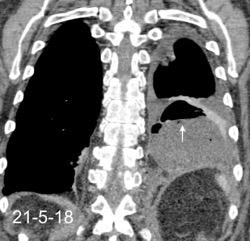

Marzo 2014: Perforación longitudinal distal secundaria a episodio de vómito (síndrome de Boerhaave). Derrame pleural izdo. que evoluciona a empiema.

Wang C-T et al. Tension hydropneumothorax in a Boerhaave syndrome patient: A case report . World J Emerg Med, 2021. Katabathina V et al. Nonvascular, nontraumatic mediastinal emergencies in adults:a comprehensive review of imaging findings. Radiographics. 2011.